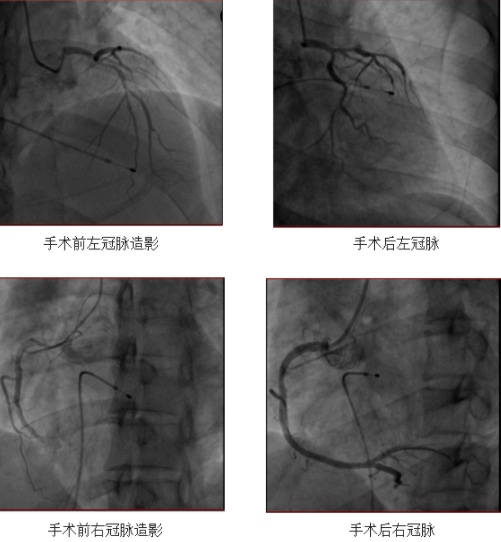

介入室内,一台消化内科手术即将开始,接到通知后立即让台给更需要手术的患者刘先生。王新云教授带领手术团队迅速进行临时起搏器安装,在起搏器的安全支持下介入医师很快为患者进行了冠状动脉造影检查。冠状动脉造影提示冠脉多支血管病变,粗大的右冠状动脉(RCA)远端完全闭塞并血栓造影。危及这位37岁年轻男性生命的疾病的“罪魁祸首”终于找到了——急性心肌梗死(RCAd)。

经过与赶来的患者家属沟通同意并签字后,手术医生立即开通闭塞的右冠脉血管,置入1枚支架后,刘先生的RCA前向血流恢复,心脏电活动恢复正常,咽痛、头晕症状消失,为了防止可能还会出现的恶性心律失常,刘先生带着临时起搏器回到了CCU病房。